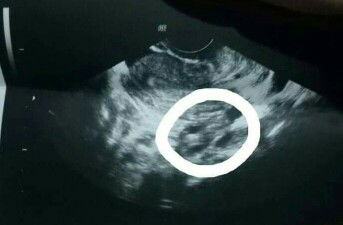

Normal po ba sya sa 7 weeks na pregnant??

naku momsh, ob sonologist and sonographer lang po makapagsabi nyan based sa scan kasi sinusukat po nila yan..saka palang po nila binibigay result sa OB para magexplain sa mommy if normal for age po laki